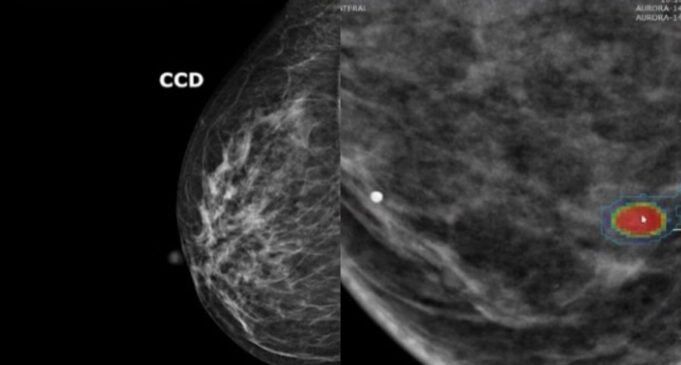

Em geral, recomenda-se uma mamografia de rastreio do cancro da mama de dois em dois anos para mulheres com idades compreendidas entre os 50 e os 74 anos. No entanto, o risco individual de desenvolver a doença – e, portanto, a necessidade de uma detecção precoce eficaz – varia consideravelmente de uma mulher para outra.